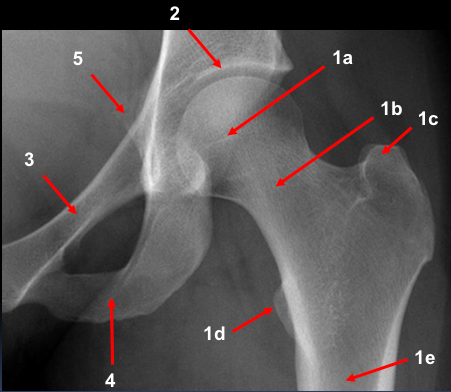

A 78 year old woman fell in her home. She could not get up again due to pain in her right groin. An ambulance was called.

An 48 year old man presented to the ED with 3-day history of left hip pain after falling in the shower. He was struggling to walk. On examination his left leg was a little shorter than the right and slightly laterally rotated.

What action would you take? Justify your course of action / investigation / management!